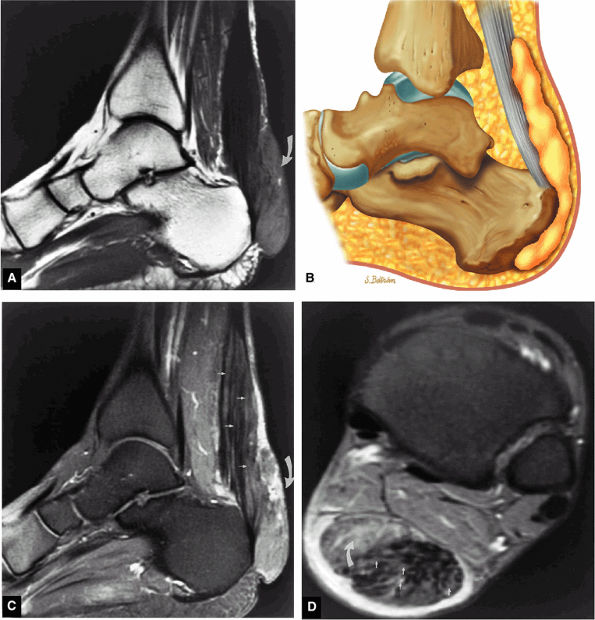

FIGURE 5.116 ● Haglund's deformity with distal Achilles tendinitis, osseous edema of the posterosuperior calcaneus, and visible fluid and/or thickening in the retrocalcaneal bursa and tendo-Achilles bursa. (A) Lateral color illustration. (B) Sagittal FS PD FSE image.

|

FIGURE 5.117 ● Excision of Haglund deformity. (A) Lateral color illustrations showing excision of the posterior superior os calcis before (top) and after (bottom) surgery. (B) Arthroscopic illustration showing image from the medial portal with lateral placement of a bur to remove the superior angle of the calcaneus.